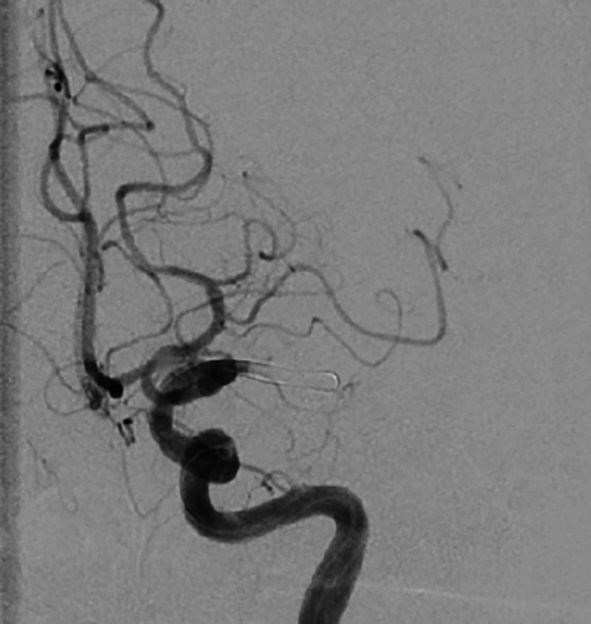

a) Verschluss der A. cerebri media links im M1-Segment | © C. Vockelmann

Der Eingriff erfolgt derzeit in der Regel in Intubationsnarkose, zunehmend auch in Analgosedierung in Intubationsbereitschaft, sollte sich der Patient klinisch verschlechtern. Auch hier gilt: Time is brain! Alle Abläufe sollten auf unnötige Handlungen überprüft und gestrafft werden. Für die Thrombektomie ist zunächst ein üblicher, steril gedeckter Angiografietisch erforderlich. Schleusenspülungen mit heparinisierter Kochsalzlösung (5.000 IE Heparin in 500 ml NaCl 0,9 %) müssen vorbereitet werden. Eine Kontrastmittelpumpe ist nicht unbedingt erforderlich, die Kontrastmittelgabe kann während der Intervention auch von Hand erfolgen. Der Zugang erfolgt über die rechte Leiste. Zunächst wird eine kurze 8F-Schleuse in der A. femoralis platziert. Hierüber wird eine 90 cm lange 6F-Schleuse oder ein 8F-Führungskatheter mit einem Vertebralis- oder Sidewinder-konfiguriertem Katheter und einem 0,035-inch-Führungsdraht in die ACI der betroffenen Seite vorgebracht. Jetzt erfolgt zunächst eine diagnostische Angiografie der intrakraniellen Gefäßstrombahn in 2 Ebenen. Sollte vor der Thrombektomie eine intravenöse Lysetherapie erfolgt sein, wird auf eine zusätzliche intraarterielle Heparingabe verzichtet, um das Blutungsrisiko nicht zu erhöhen. Für die Thrombektomie gibt es verschiedene Verfahren. Wichtiges Ziel aller Techniken ist neben der Wiederherstellung der Perfusion eine Vermeidung der Thrombusfragmentation mit Verschleppung in weiter distal gelegene Gefäßabschnitte oder auch neue, bisher nicht betroffene Gefäßterritorien.

Der Einsatz eines Stentretrievers ist die bisher am häufigsten eingesetzte Technik. Hierbei handelt es sich letztlich um einen modifizierten intrakraniellen Stent, der an einem 0,014-inch-Draht befestigt ist. Der Thrombus wird mit einem 0,014-inch-Mikrodraht und einem 0,021-inch-Mikrokatheter passiert. Über den Mikrokatheter wird der Stentretriever im Thrombus freigesetzt, der Blutfluss nach distal ist jetzt wiederhergestellt. Nach einer Wartezeit von 5–8 Minuten, in der sich der Thrombus in den Stentmaschen festsetzen soll, wird der Stentretriever entfaltet zurückgezogen. Damit der Stentretriever ohne Abscheren des Thrombus in der langen Schleuse geborgen werden kann, muss eine Schleuse mit abschraubbarem Ventil verwendet werden. Bei der Adapt-Technik (direct aspiration first-pass thrombectomy) wird ein großlumiger Aspirationskatheter direkt vor den Thrombus gebracht, bei einem Verschluss der proximalen A. cerebri media wird dazu ein 6F-Katheter verwendet. Über eine Aspirationspumpe wird dann der Thrombus in den Katheter gesaugt. Nach frühestens 90 s wird, falls der Thrombus nicht komplett aspiriert werden kann, der Aspirationskatheter unter Sog mit dem Thrombus an der Katheterspitze zurückgezogen. Bei der Solumbra-Technik, benannt nach ihrem Erstbeschreiber, wird ein Stentretriever-Manöver mit einem Aspirationskatheter, der bis an den Thrombus herangeführt wird, kombiniert. Eine Weiterentwicklung der Solumbra-Technik ist die SAVE-Technik (stent retriever assisted vacuum-locked extraction). Der Stentretriever wird zu 2/3-Dritteln distal des Thrombus freigesetzt. Hierdurch wird ebenso wie durch das Rückholen in einen Aspirationskatheter das Risiko einer distalen Embolisation verringert.